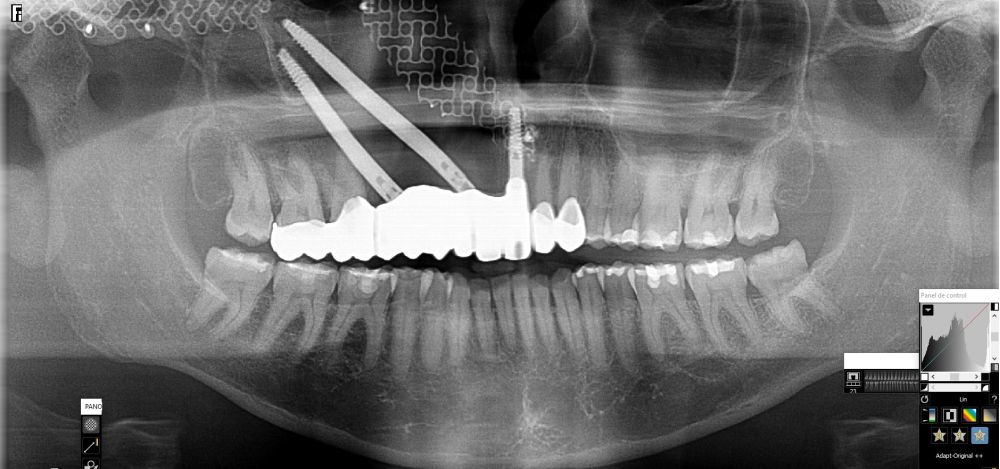

Bajo anestesia general, se realizó la resección quirúrgica junto con la fijación de dos placas preformadas y colocación simultánea de dos implantes cigomáticos y un implante endoóseo en posición del 2.1 (Figuras 5 y 6). Debido a la presencia de márgenes quirúrgicos comprometidos en el informe anatomopatológico, se indicó la administración de radioterapia adyuvante. Por este motivo, se decidió realizar un puente provisional dentosoportado de 1.7 a 2.3 (Figura 7) para mejorar la situación estética y funcional de la paciente durante todo el proceso y evitar un colapso de los tejidos blandos por la radioterapia. Para ello, se tallaron los molares (1.7, 1.6) e incisivo lateral y canino (2.2, 2.3), y se fabricó un puente fresado en polimetilmetacrilato (PMMA) con refuerzo metálico (Figuras 8 y 9).

Una vez finalizada la radioterapia, la paciente se encontraba libre de enfermedad. Por lo que se procedió a la restauración definitiva implantosoportada. Tras la segunda fase, se colocaron dos pilares transepiteliales Multiunit Ò rectos y un pilar Multunit Ò angulado de 17º (Figura 10).

Finalizado el tratamiento oncológico y confirmada la ausencia de enfermedad activa, se procedió a la segunda fase quirúrgica con la colocación de pilares transepiteliales Multiunit®. La integración de los implantes cigomáticos y del implante endoóseo fue satisfactoria, observándose estabilidad clínica y ausencia de signos de periimplantitis.

Las impresiones analógicas y el posterior flujo digital permitieron una correcta planificación protésica. Las estructuras definitivas, confeccionadas en óxido de zirconio monolítico sobre interfases metálicas de titanio, mostraron una adecuada adaptación pasiva tanto clínica como radiográficamente. La prueba estética permitió ajustes oclusales y funcionales mínimos, optimizando el resultado final.

En el seguimiento a 4 años tras la colocación de la prótesis definitiva, no se observaron complicaciones mecánicas ni biológicas. La paciente continúa libre de enfermedad y con una correcta adaptación al tratamiento rehabilitador implantosoportado (Figura 18).